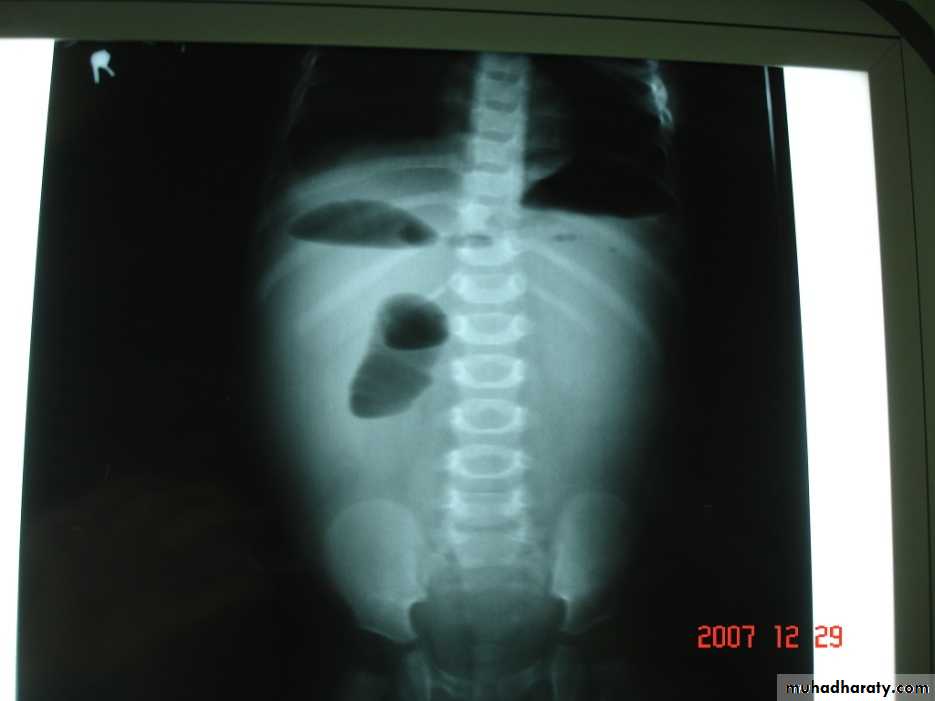

P/R:Dx.1. Plain radiograph